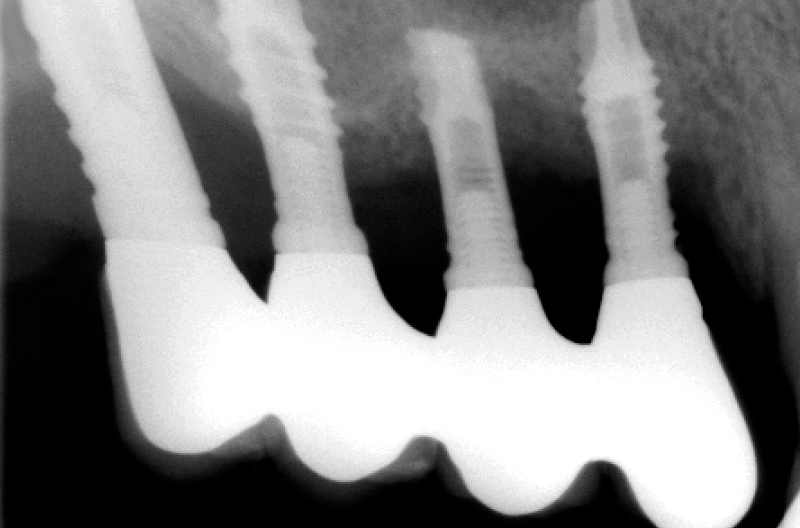

La paziente accusa fastidio generalizzato alle gengive con saltuario dolore in alcuni distretti, sanguinamento spontaneo e alla spazzolatura, difficoltà nelle manovre igieniche, difficoltà masticatoria, estetica insoddisfacente. Le immagini cliniche e radiografiche (Figg. 1-7) mostrano come il risultato finale sia dovuto a non corretta formulazione del piano di trattamento e a non corretta esecuzione delle procedure chirurgiche e protesiche. Il posizionamento errato degli impianti nei tre piani dello spazio comporta l’esposizione delle spire, in particolare sul versante vestibolare, impedendo la formazione di una ampiezza biologica adeguata a preservare l’osso peri-implantare. La mancanza o la scarsità di gengiva aderente costituisce ulteriore fattore di aggravamento del quadro. Noi sappiamo che per poter eseguire una implantologia in un unico tempo dobbiamo essere in presenza di una adeguata banda di mucosa aderente (Warrer et al 1995; Schrott et al 2009).

- Fig. 3 – Le radiografie endorali di fine trattamento evidenziano una incongruità della protesi, che appare sollevata nei settori posteriori.Tale condizione determina una impossibilità alla detersione a livello della connessione implant-abutment con conseguente accumulo di placca e compromissione dell’ampiezza biologica